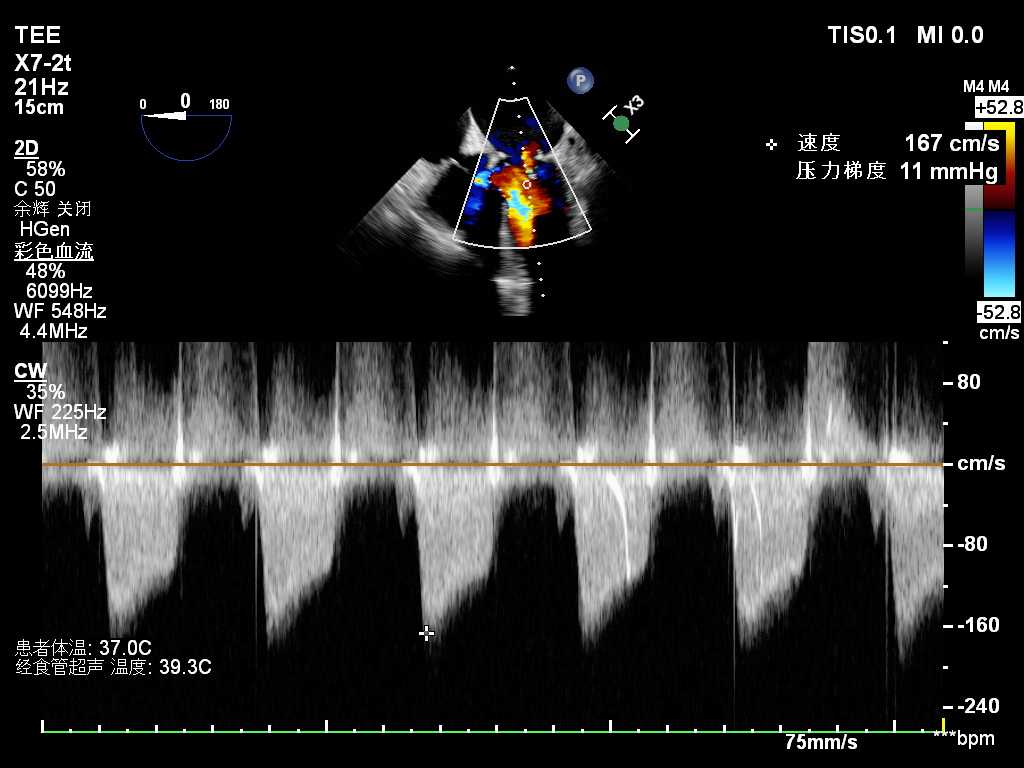

张海波教授接诊王女士后,对其心脏瓣膜情况进行了详细评估,认为修复可能性很大。手术由张海波教授亲自主刀,在体外循环下,精细清除瓣叶钙化组织,将增厚瓣叶逐层削薄,小心切开瓣交界粘连,同时将二尖瓣后叶予以补片加宽,置入成形环,整个过程如行云流水,一气呵成。试水见瓣膜关闭良好,术中同时为患者施行了房颤外科消融手术。术后心脏恢复良好,食道超声提示:二尖瓣成形效果理想,仅见微量反流,心律也恢复为正常窦性。

一台成功的成形术离不开外科医生、麻醉师、体外循环师、超声医师的紧密配合,术中需借助经食管超声实时监测修复效果,确认瓣膜反流是否消除、开闭是否正常,有时甚至需在心脏复跳后再次评估,若效果不佳还要再次停跳调整,这对整个团队的默契度与协同能力提出了极高要求。